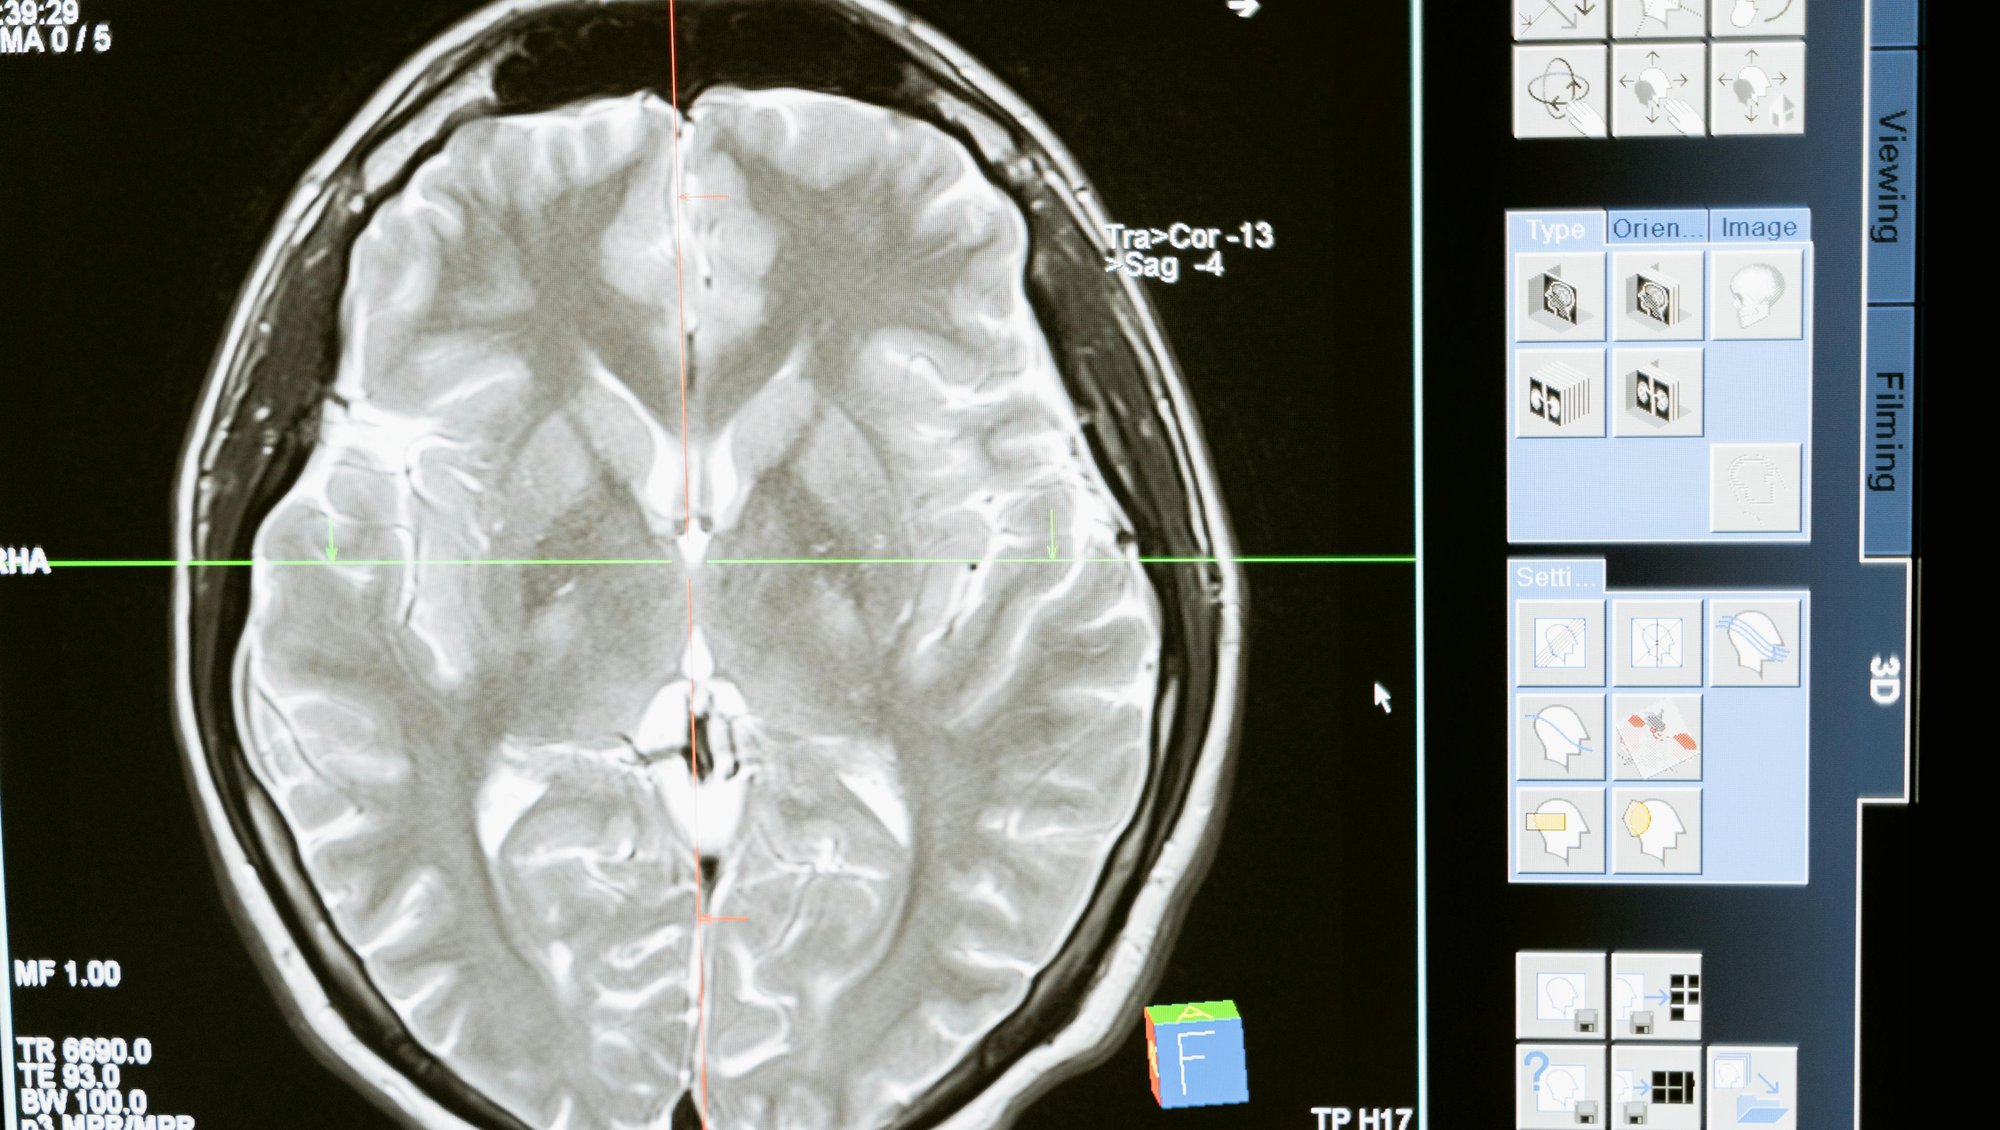

Beyin Kan Akımı, Serebral Perfüzyon ve Cerrahi Sırasında Dokuların Korunması

Beyin cerrahisi sırasında, beynin oksijen alımını sağlamak hayati bir öneme sahiptir. Kan akışı kesilirse veya yetersiz olursa, beyin hücreleri dakikalar içinde ölmeye başlar. Bu yüzden bir nöroşirürjiyenin en önemli görevlerinden biri, beyin kan akımını (CBF) ve serebral perfüzyon basıncını (CPP) cerrahi boyunca optimum seviyede tutmaktır.